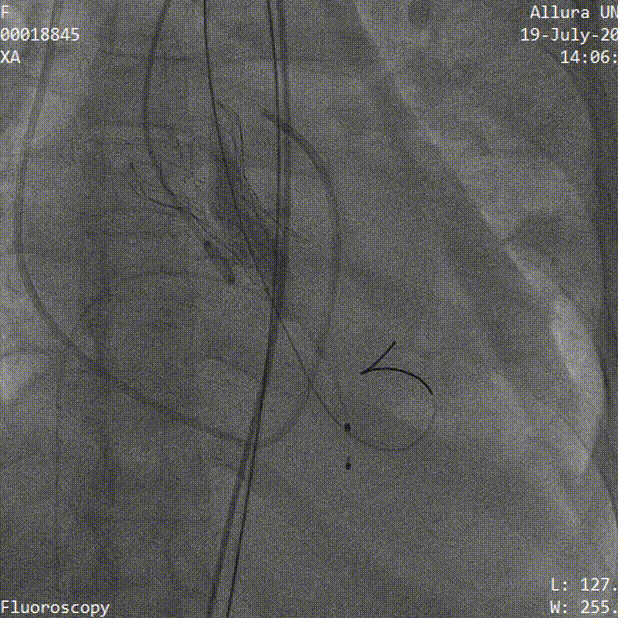

3.TaurusElite AV26号瓣膜定位及释放。瓣膜初始定位瓣下2mm,开花后120次起搏,释放到工作位后造影显示锚定充足,位置良好,冠脉未见遮挡,继续缓慢旋转手柄,瓣膜逐一脱钩,顺利释放。

瓣膜初始定位

瓣膜释放过程

瓣膜脱钩